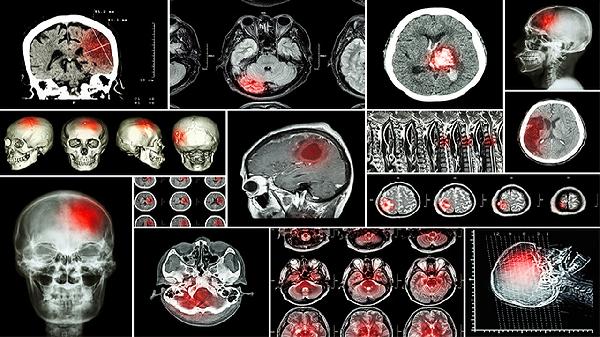

气管肿瘤的生存期与肿瘤类型、分期、治疗方法及个体差异密切相关,早期发现和规范治疗可显著提高生存率。

气管肿瘤分为良性和恶性,良性肿瘤如软骨瘤、纤维瘤,通常生长缓慢,手术切除后预后良好,生存期较长。恶性肿瘤如鳞状细胞癌、腺样囊性癌,侵袭性强,生存期较短,但通过手术、放疗、化疗等综合治疗,仍可延长生存时间。

肿瘤分期是影响生存期的重要因素,早期肿瘤局限在气管内,手术切除后5年生存率可达60%-80%。中晚期肿瘤侵犯周围组织或远处转移,治疗难度大,生存期相对较短,但通过个体化治疗方案,仍可改善生活质量。

手术是气管肿瘤的主要治疗手段,包括气管部分切除术、气管重建术等,早期手术可显著提高生存率。放疗适用于无法手术的患者,可控制肿瘤生长,缓解症状。化疗主要用于晚期患者,可延长生存期,改善生活质量。